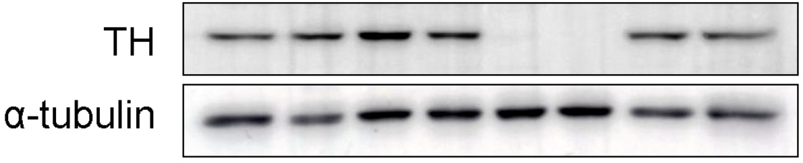

신경면역학 실험실(Neuroimmunology Laboratory)은 신경계와 다양한 말초조직 간의 상호작용을 연구합니다. 특히 말초조직 또는 면역세포를 조절하는 자율신경 신경회로를 발굴하고 작용기전을 밝힘으로써, 대사장애, 만성 염증성 질환, 종양, 근감소증 등을 극복하는 연구를 수행합니다.

뇌-말초조직 네트워크 규명을 위한 신경회로 발굴 및 제어연구

신경계-면역계 상호작용 연구

뇌혈관장애 및 퇴행성뇌질환 개선연구

근육-뇌, 지방조직-뇌 상호작용 제어를 통한 시스템 에너지대사 조절연구